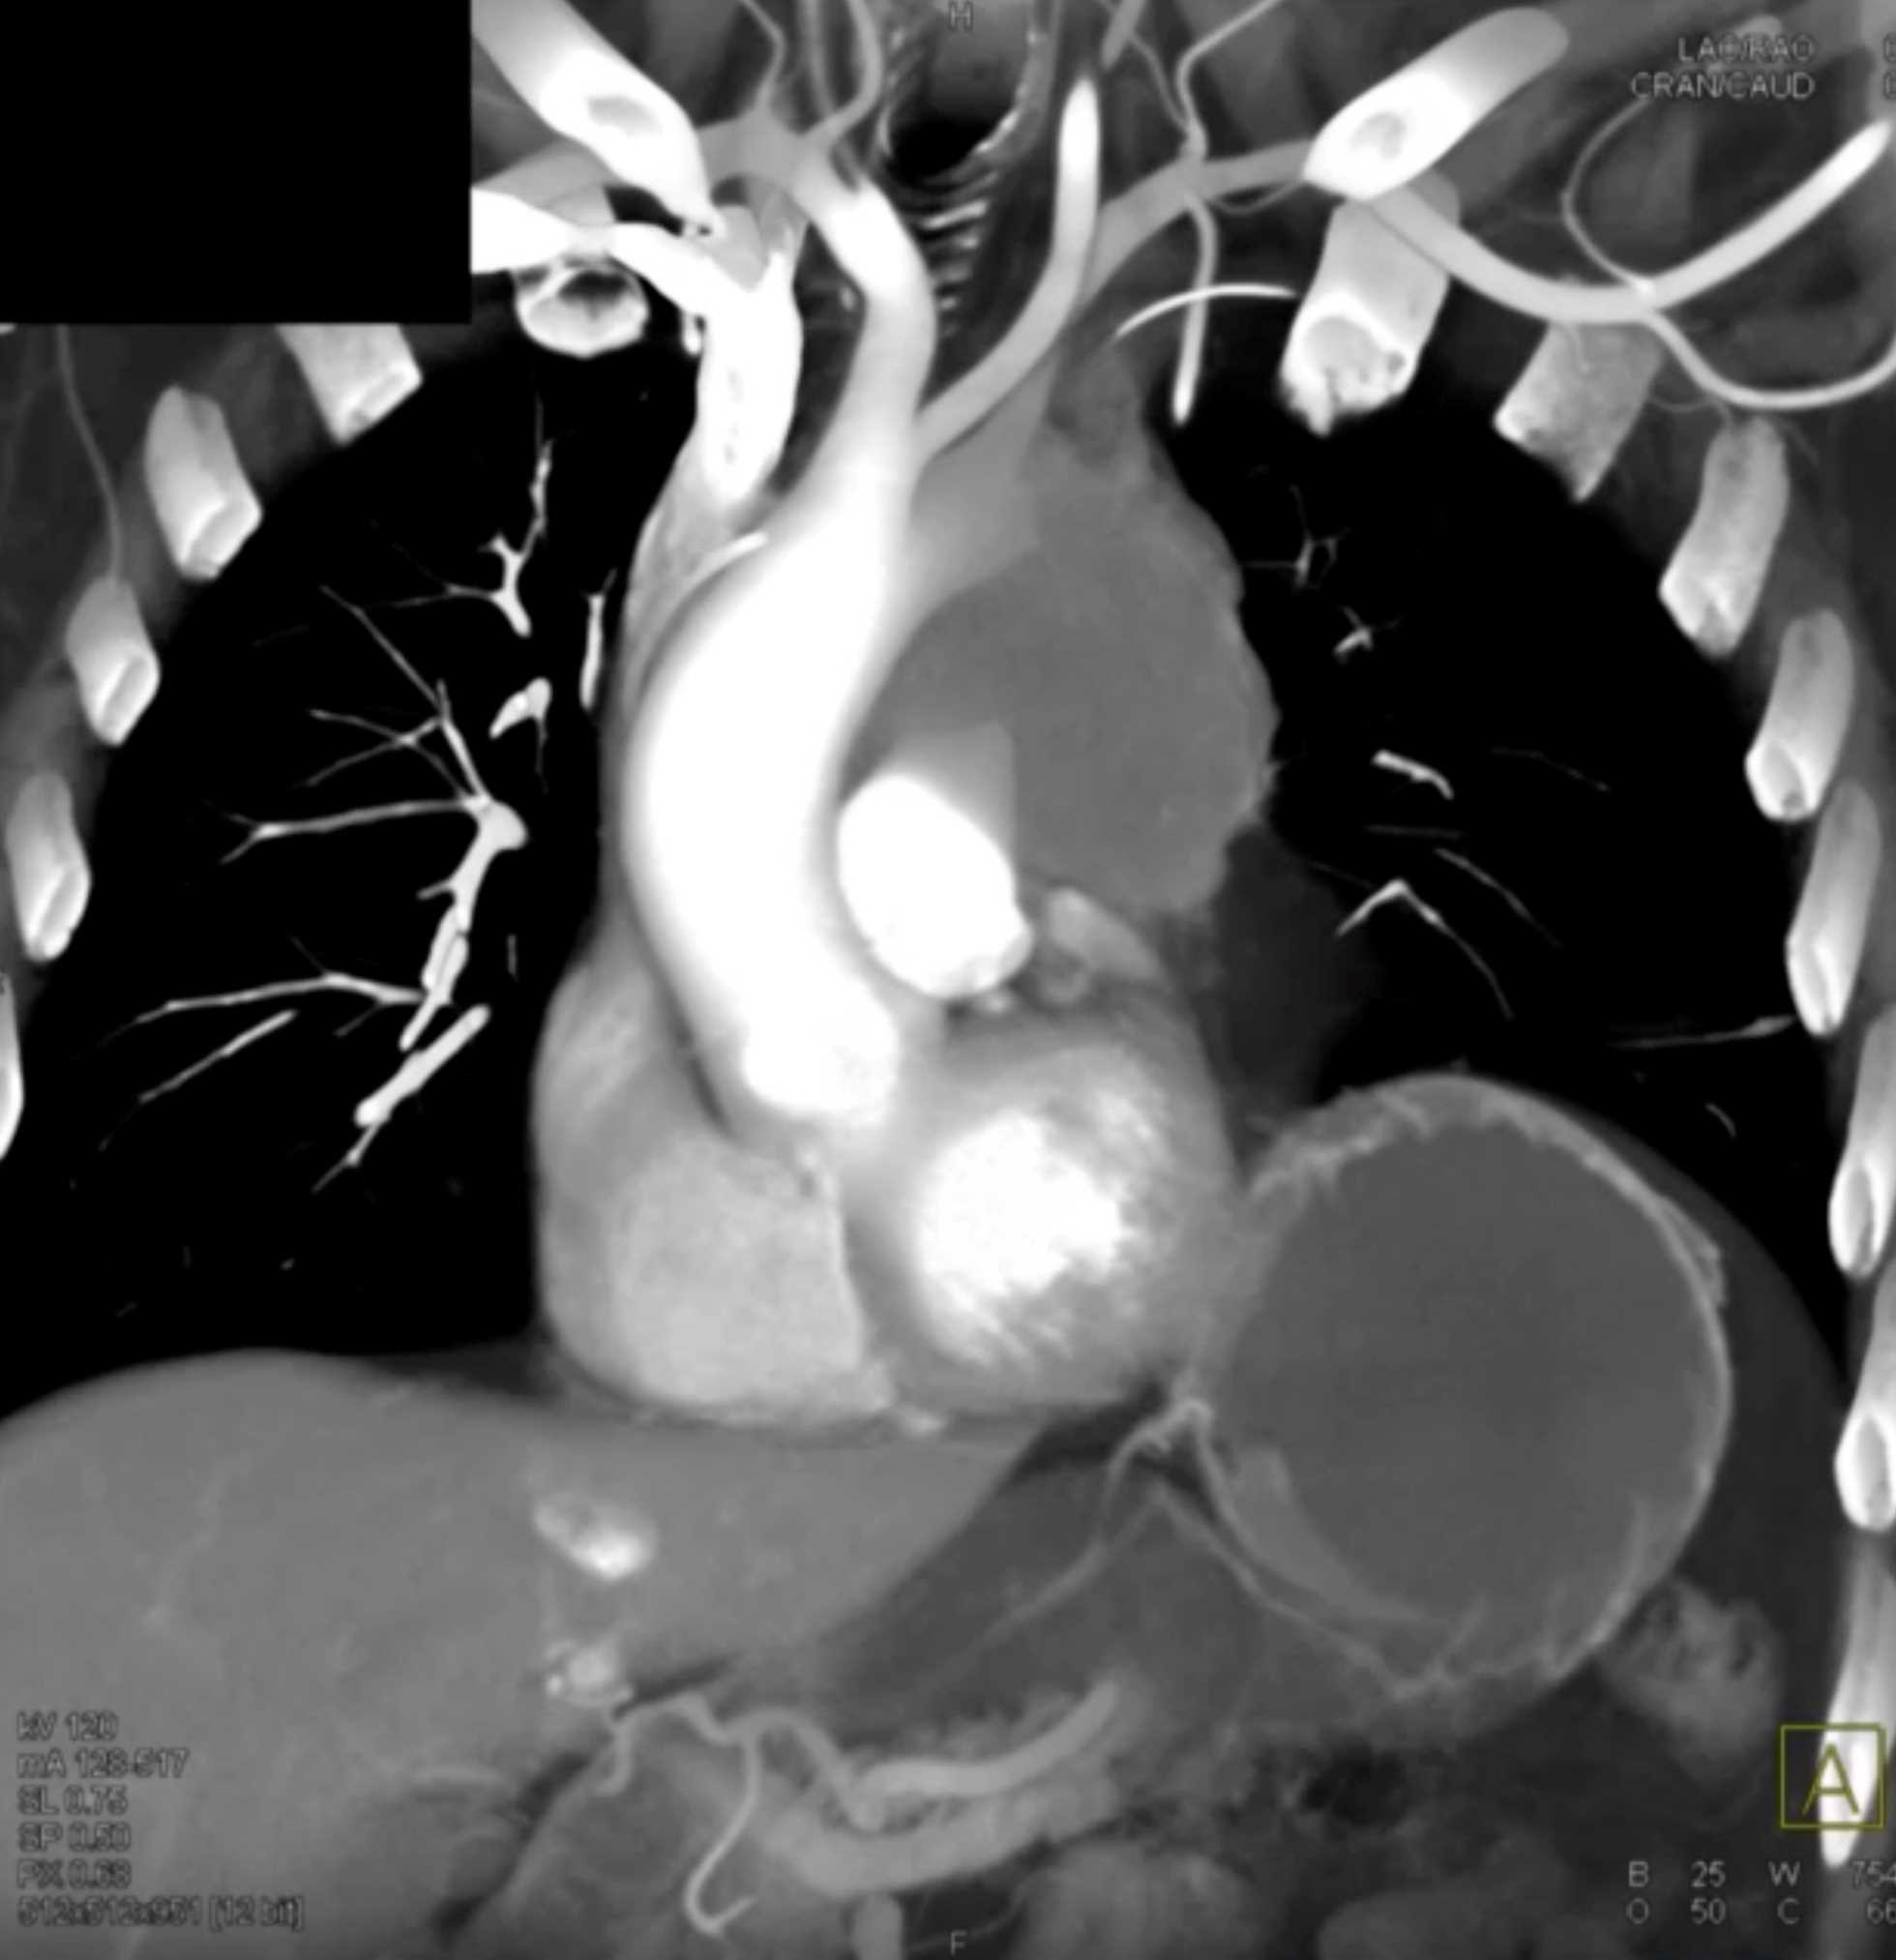

Thymic Carcinoma